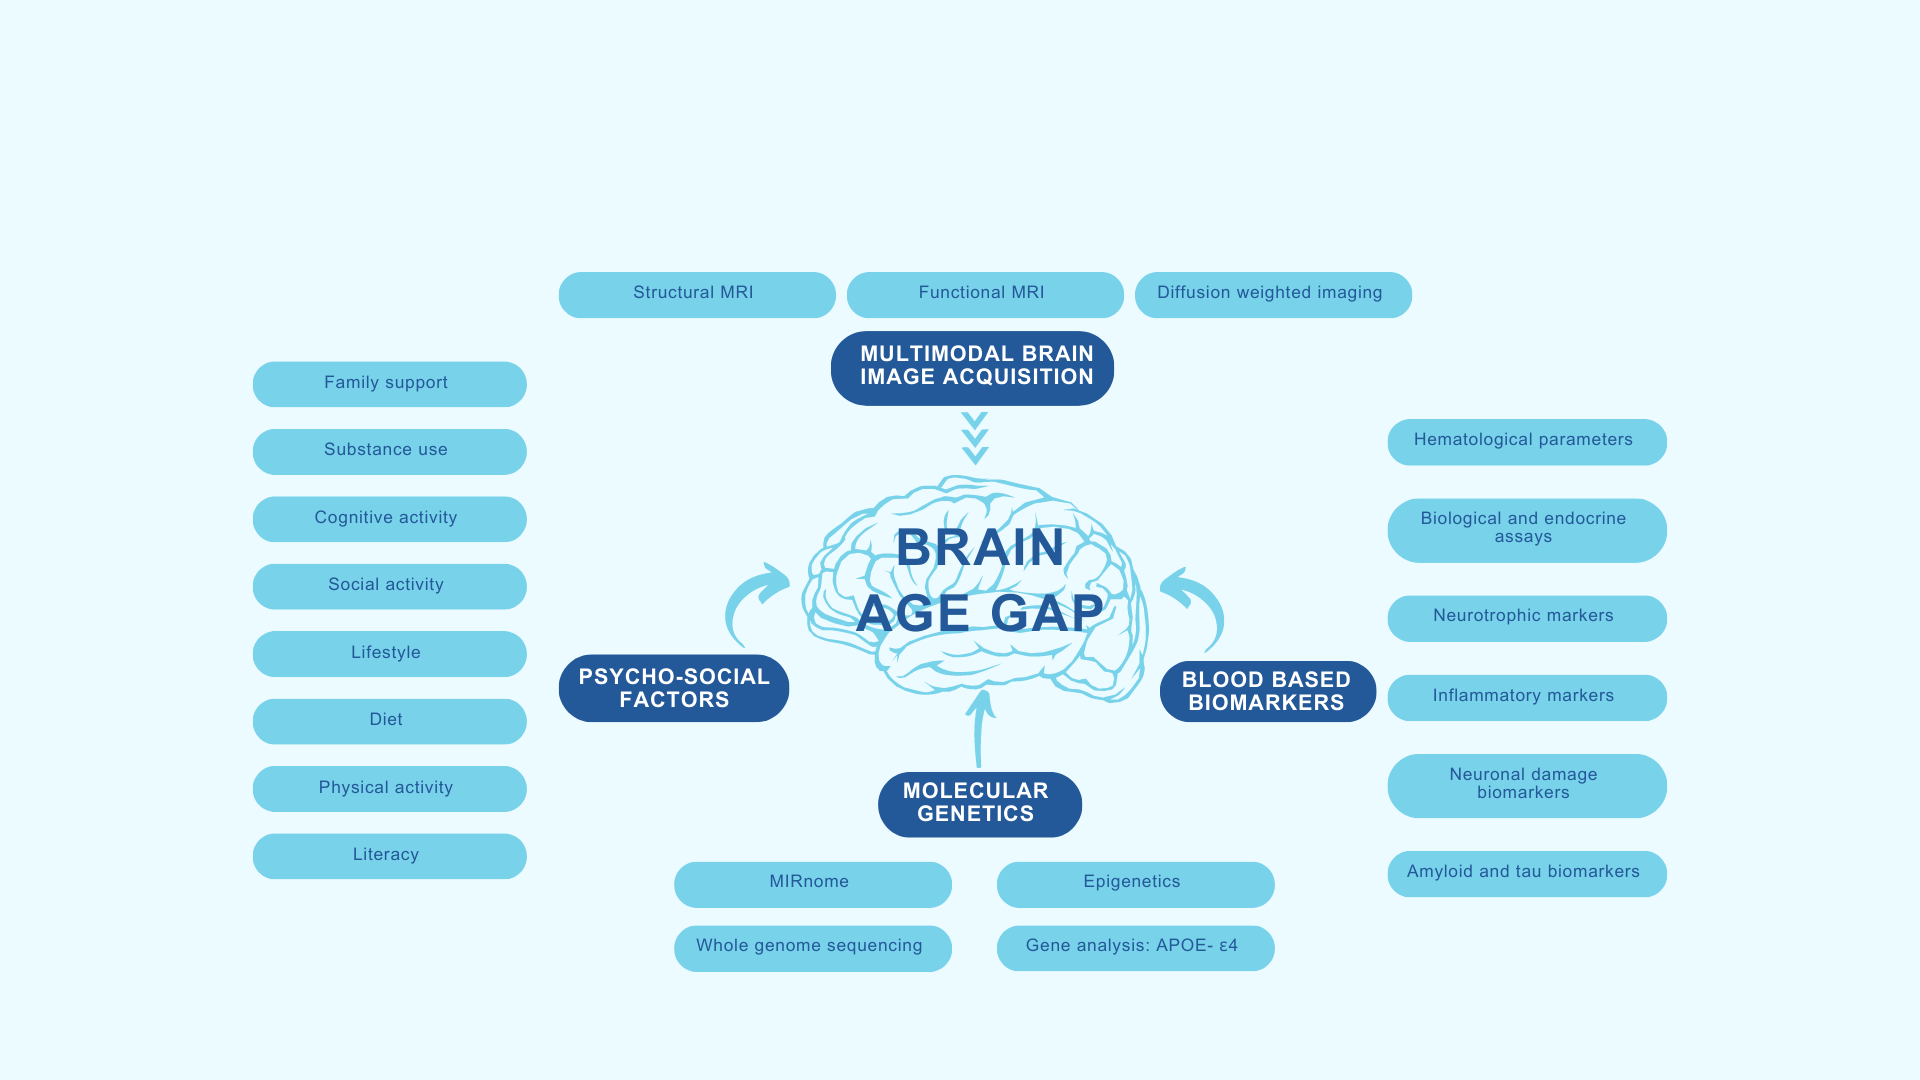

In this innovative research study, we will first evaluate our research participants [Healthy elders, persons with Alzheimer’s dementia, and persons with Mild Cognitive Impairment (MCI—a stage between normal cognitive functioning and dementia), who volunteer to participate in the research] for various psychosocial and lifestyle factors, for e.g., educational attainment, dietary habits, physical activity, family support, etc., Then we will evaluate them using a comprehensive series of tests to detect their functioning in memory and other thinking abilities. We will also be looking at various biomarkers – genetic, hormonal, markers of cardiovascular risk, and brain imaging. We will follow up our participants over two years to determine how the interplay of various risk factors, protective factors, blood-based and brain imaging-based biomarkers influence their cognitive function and contribute to the risk for developing dementia. We plan to establish the above relationship between various lifestyle factors, biomarkers and risk for dementia using a novel brain metric called ‘brain age’, which is an estimate of the person’s age computed from brain imaging measures using magnetic resonance imaging (MRI). By estimating the ‘brain age gap’ between a person’s actual age and the ‘brain age’, we can study the factors that result in accelerated brain aging in persons with dementia.

The campus recently announced the launch of a new collaborative initiative centered around the prediction of brain age gap using brain imaging.